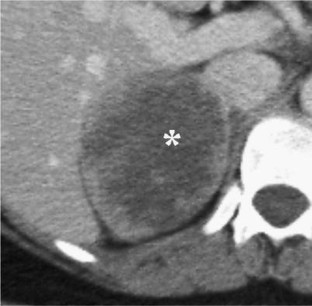

Benign OANs were smaller [mean size 3.7 cm (range 2.6–5.3)] and more homogeneous than malignant OANs and demonstrated greater washout [mean washout percentage 72.3% (range 61–88)]. Malignant OANs demonstrated features similar to ACCs, including size [mean 9.4 cm (range 5.2–9.8)] and internal necrosis (n = 6). Mean enhancement washout percentage for malignant OANs was 12% (range −8 to 32).

Benign OANs (oncocytomas) may be distinguished from lipid-rich adenomas on non-contrast CT but may be indistinguishable from lipid-poor adenomas. Malignant oncocytic neoplasms can demonstrate features similar to ACCs, including larger size, internal necrosis, and lower percentage enhancement washout.